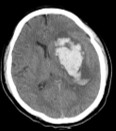

脳内出血、脳室内出血

内視鏡による脳内出血の治療は最近発展している治療です。局所麻酔、場合によっては全身麻酔で低侵襲かつ血腫除去効果の高い手術が可能です。

脳出血の場合、神経内視鏡を用いる手術では頭蓋骨に小さな孔を開け、周囲を観察しながら血腫を取り除くことができます。従来の開頭手術に比べ、患者さんの負担は少なく、リハビリも早くから始められます。

脳出血における神経内視鏡手術前後の画像